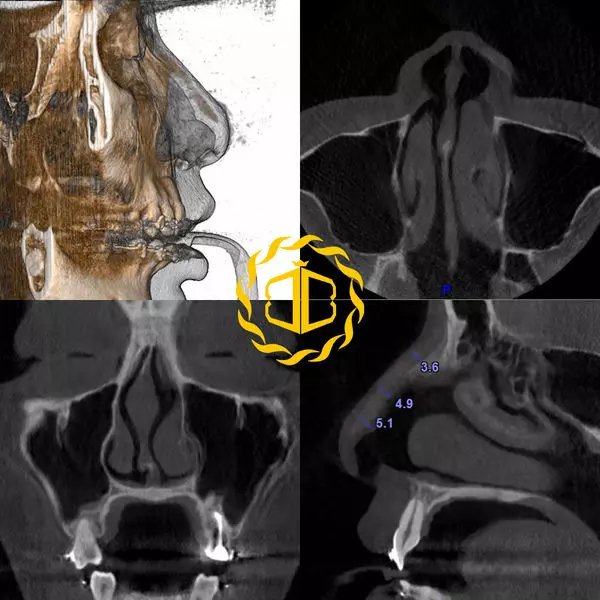

乐乐鼻子外观也符合上述的种种问题,同时利用博恩妍诊所的3D电脑断层显示她鼻中隔歪曲的相当严重。

所以手术规划如下↓↓↓

- 移除I型假体

- 歪鼻调整(鼻中隔弯曲调整与鼻骨截骨)

- 全自体软骨鼻头(微翘鼻头,尖中带圆的型态)

- 荚膜放松,正确假体放置层次建立

- ePTFE鼻膜放置

术后乐乐改善了严重假体歪斜,鼻头不明显问题,同时高挺却略带弧度的鼻梁,微翘的鼻头,是时下年轻女孩美鼻完美典范